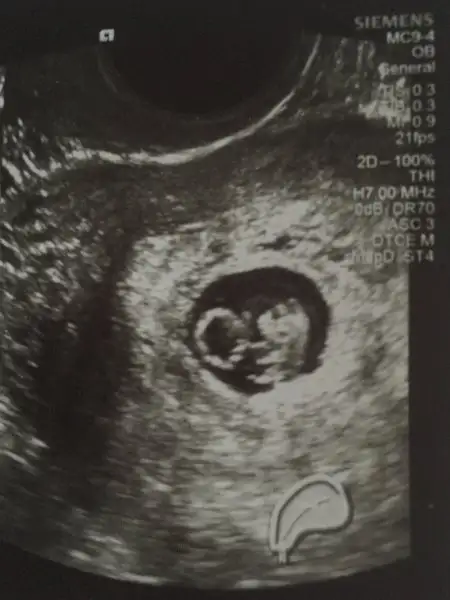

Çok net maşallah kız bebek olabilir bu:)